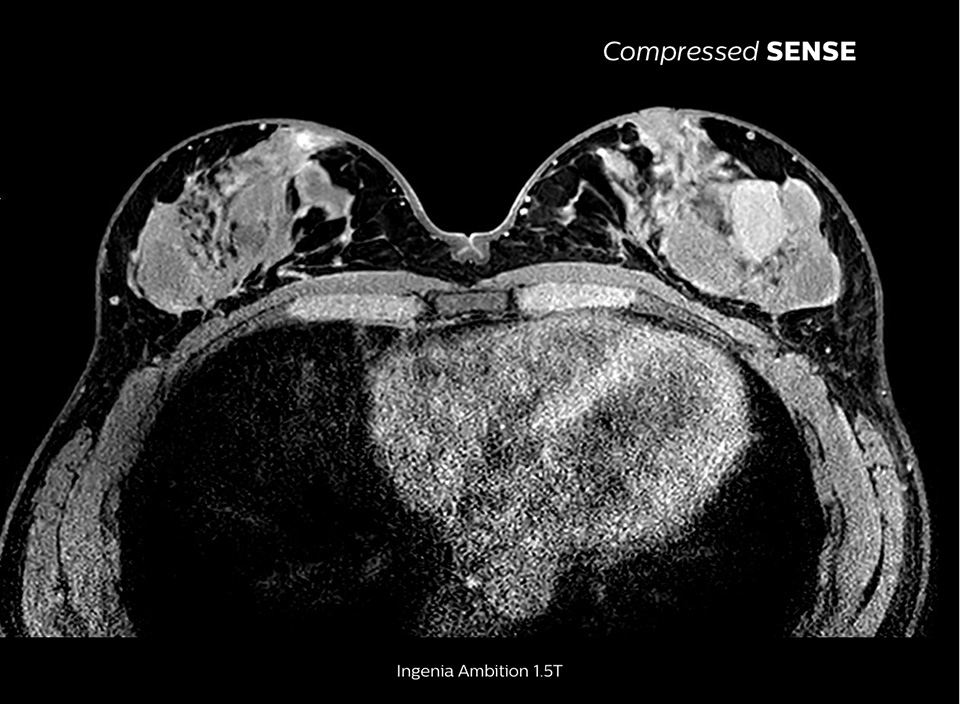

Up to 50% faster 3D sequences, with virtually equal image quality1

Compare the time savings of an MRI scan performed with Compressed SENSE MRI software versus a conventional scanning technique

The MRI staff at Kurashiki Central Hospital incorporated Compressed SENSE into most of the brain, spine, abdominal, and cardiac examination protocols on their Ingenia 1.5T, resulting in fast and high-quality MRI scans, which is welcomed by patients and staff.